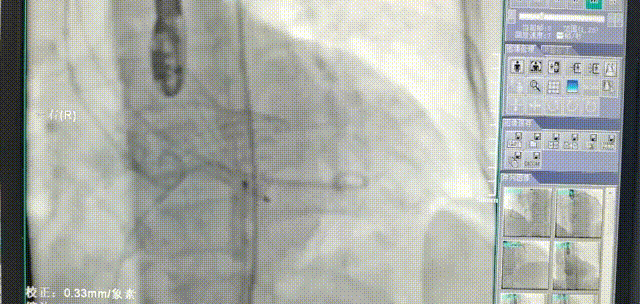

根部造影测量瓣环径

29#瓣膜释放后明显下滑,瓣周漏明显,与术前预计一致。

使用瓣中瓣技术,29#瓣膜与第一个瓣膜同位释放,瓣周漏消失。